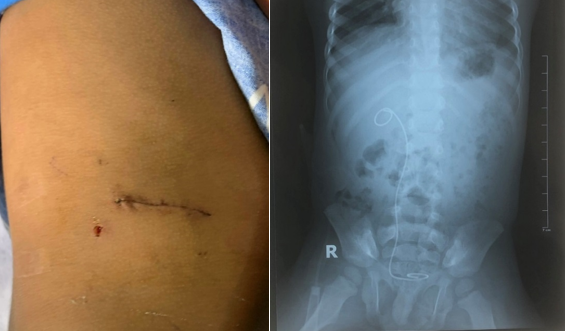

Hình 3. Vết mổ và hình ảnh chụp Xquang sonde JJ lưu trong niệu

quản.

Các bác sĩ đã tiến hành

cắt bỏ đoạn hẹp dài 1,5cm và khâu tạo hình lại khúc nối bể thận niệu quản có

đặt ống thông sonde JJ giúp định hình đoạn hẹp. Ca phẫu thuật thực hiện thành

công sau khoảng 40 phút, chiều cùng ngày bệnh nhân đã tỉnh, ăn uống được và

phục hồi các vận động bình thường.

Sau mổ, bệnh nhân không

còn bị đau tức phần bụng và thắt lưng, sức khỏe phục hồi tốt. Dự kiến bệnh nhân

sẽ được xuất viện sau khoảng 7 ngày điều trị, ống JJ sẽ được rút sau khoảng 3-4

tuần qua nội soi Bàng quang.